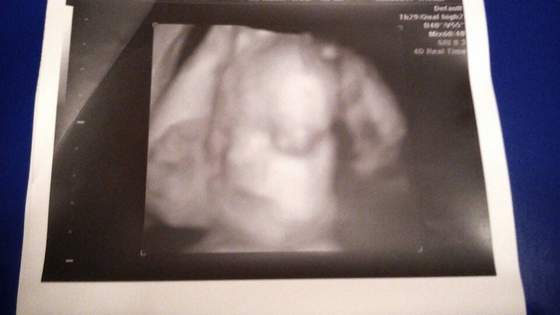

Kochane ciocie oto Maciek :-)

Waży już uwaga uwaga 1162g!!! Czyli szykuje mi się wielkolud :-) znowu wyprzedzamy wszelkie pomiary na obecny tc. Zaczynam bać się porodu :-) a poza tym wszystkie przepływy szyjka wody łożysko ok.

Załączniki

• 1409256032359.jpg

1409256032359.jpg

12,4 KB · Wyświetleń: 86